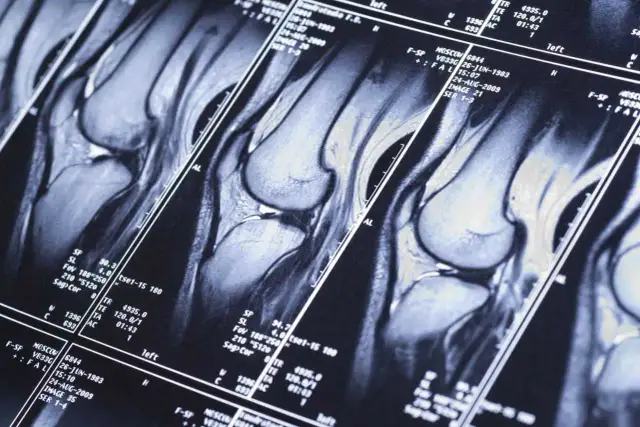

Neurologowie korzystają z różnych badań diagnostycznych, aby zidentyfikować problemy związane z układem nerwowym. Do najczęściej stosowanych metod należą tomografia komputerowa (CT), rezonans magnetyczny (MRI) oraz elektroencefalografia (EEG). Każda z tych metod ma swoje unikalne zastosowanie i pozwala na uzyskanie szczegółowych informacji na temat stanu zdrowia pacjenta. Właściwy dobór testów diagnostycznych jest kluczowy dla postawienia trafnej diagnozy.

Tomografia komputerowa (CT) jest często stosowana do oceny urazów głowy oraz wykrywania guzów mózgu. Rezonans magnetyczny (MRI) z kolei dostarcza bardziej szczegółowych obrazów struktur mózgu i rdzenia kręgowego, co czyni go niezastąpionym w diagnostyce chorób takich jak stwardnienie rozsiane. Elektroencefalografia (EEG) jest natomiast wykorzystywana do monitorowania aktywności elektrycznej mózgu, co jest istotne w diagnostyce padaczki i innych zaburzeń neurologicznych. Neurologowie często łączą te badania, aby uzyskać pełniejszy obraz stanu zdrowia pacjenta.

Rezonans magnetyczny (MRI) jest bardziej szczegółowy niż CT i nie wykorzystuje promieniowania. Jest idealny do diagnostyki chorób takich jak stwardnienie rozsiane, guzy mózgu czy uszkodzenia rdzenia kręgowego. Elektroencefalografia (EEG) natomiast, pozwala na ocenę aktywności elektrycznej mózgu, co jest kluczowe w diagnostyce padaczki oraz zaburzeń snu. Te badania pomagają neurologom w postawieniu trafnej diagnozy i dobraniu odpowiedniego leczenia.

| Rezonans magnetyczny (MRI) | Szczegółowe obrazy mózgu i rdzenia kręgowego | Stwardnienie rozsiane, guzy mózgu |